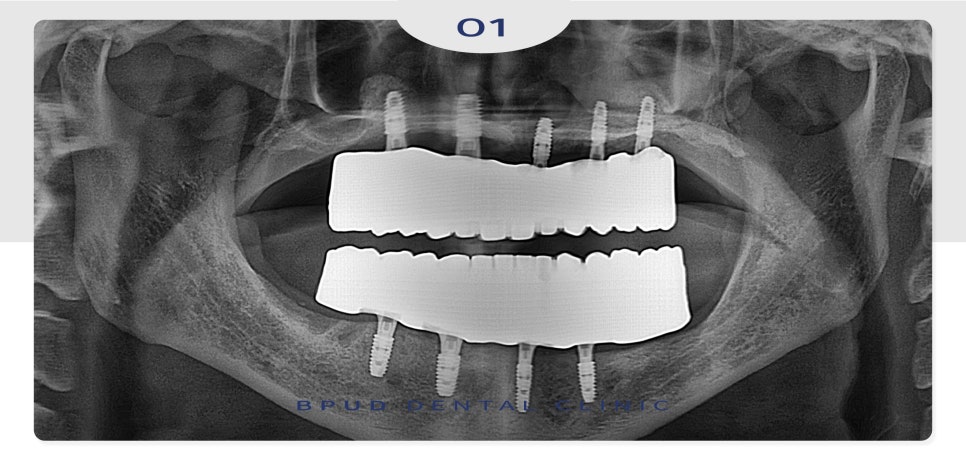

약 4개월 후 최종 보철물까지

마무리를 하였는데요.

부평치과 부평유디치과

정기검진 내원 시 사진입니다.

기존의 틀니보다 훨씬 편하고

심미적이며, 식사도 잘 하시게 되어

환자분의 만족도도 매우 높았습니다.